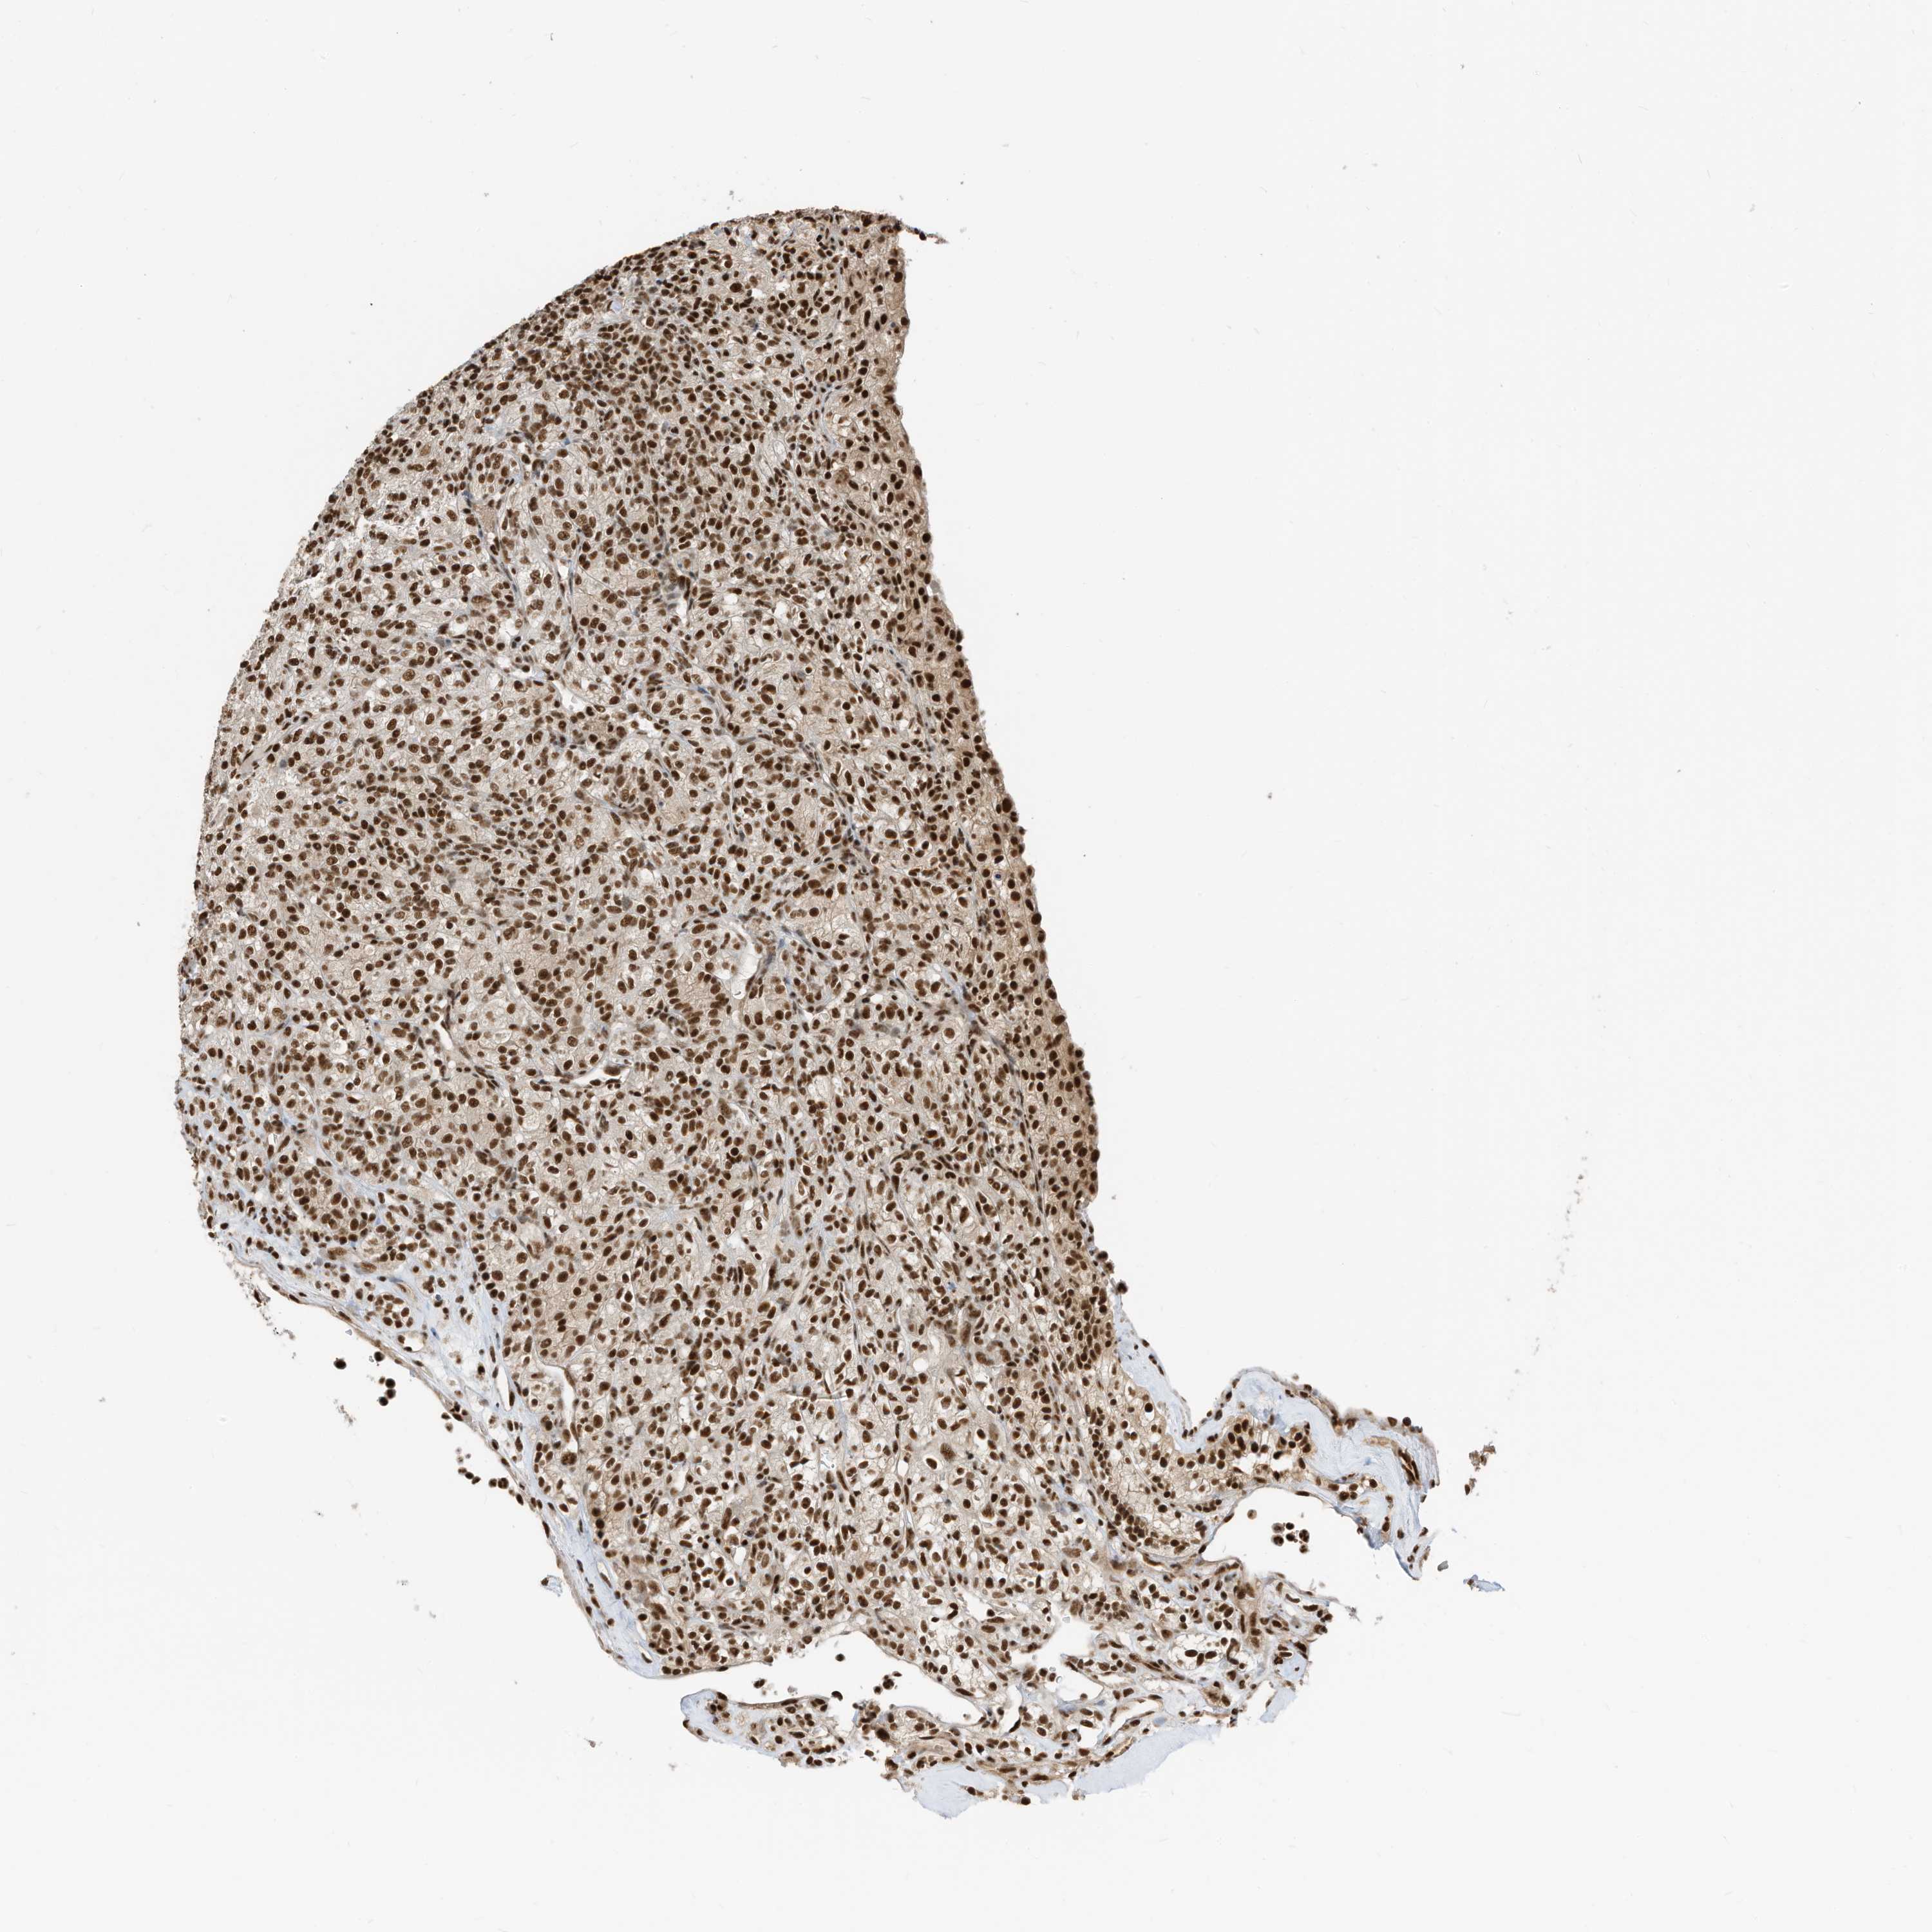

KIDNEY RENAL CLEAR CELL CARCINOMA (TCGA) - Interactive survival scatter ploti

The Survival Scatter plot shows the clinical status (i.e. dead or alive) for all individuals in the patient cohort, based on the same data that underlies the corresponding Kaplan-Meier plots. Patients that are alive at last time for follow-up are shown in blue and patients who have died during the study are shown in red.

The x-axis shows the expression levels (FPKM) of the investigated gene in the tumor tissue at the time of diagnosis. The y-axis shows the follow-up time after diagnosis (years). Both axes are complimented with kernel density curves demonstrating the data density over the axes. The top density plot shows the expression levels (FPKM) distribution among dead (red) and alive patients (blue). The right density plot shows the data density of the survived years of dead patients with high and low expression levels respectively, stratified using the cutoff indicated by the vertical dashed line through the Survival Scatter plot. This cutoff is automatically defined based on the FPKM cutoff that minimizes the p-score. The cutoff can be changed by dragging the vertical line or by entering a cutoff value in the square labeled "Current cut-off".

Under the Survival Scatter plot the p-score landscape (black curve; left axis) is shown together with dead median separation (red curve; right axis). Dead median separation is the difference in median mRNA expression between patients who have died with high and low expression, respectively. It is calculated as follows: median FPKM expression of dead patients with high expression - median FPKM expression of dead patients with low expression. This is intended to aid the user in visually exploring custom cutoffs and the associated p-scores and dead median separation.

Individual patient data is displayed and can be filtered by clicking on one or more of the category buttons on the top of the page. Categories describing expression level and patient information include: high, low, alive, dead, female, male and tumor stages. The scale of the x-axis can be toggled between linear and log-scale by clicking on the "x log" button. Mouse-over function shows TCGA ID, patient information and mRNA expression (FPKM) for each patient.

& Survival analysisi

Kaplan-Meier plots summarize results from analysis of correlation between mRNA expression level and patient survival. Patients were divided based on level of expression into one of the two groups "low" (under cut off) or "high" (over cut off). X-axis shows time for survival (years) and y-axis shows the probability of survival, where 1.0 corresponds to 100 percent.

SF3A3 is potential prognostic, high expression is favorable in Kidney Renal Clear Cell Carcinoma (TCGA)

Best expression cut offi

: 26.64

P scorei

N/A

TCGA RNA samplesi

RNA-seq data is reported as average FPKM (number Fragments Per Kilobase of exon per Million reads), generated by the The Cancer Genome Atlas (TCGA) .

Normal distribution across the dataset is visualized with box plots, shown as median and 25th and 75th percentiles. Points are displayed as outliers if they are above or below 1.5 times the interquartile range. FPKM values of the individual samples are presented next to the box plot.

Average pTPM 35.7

Number of samples 521